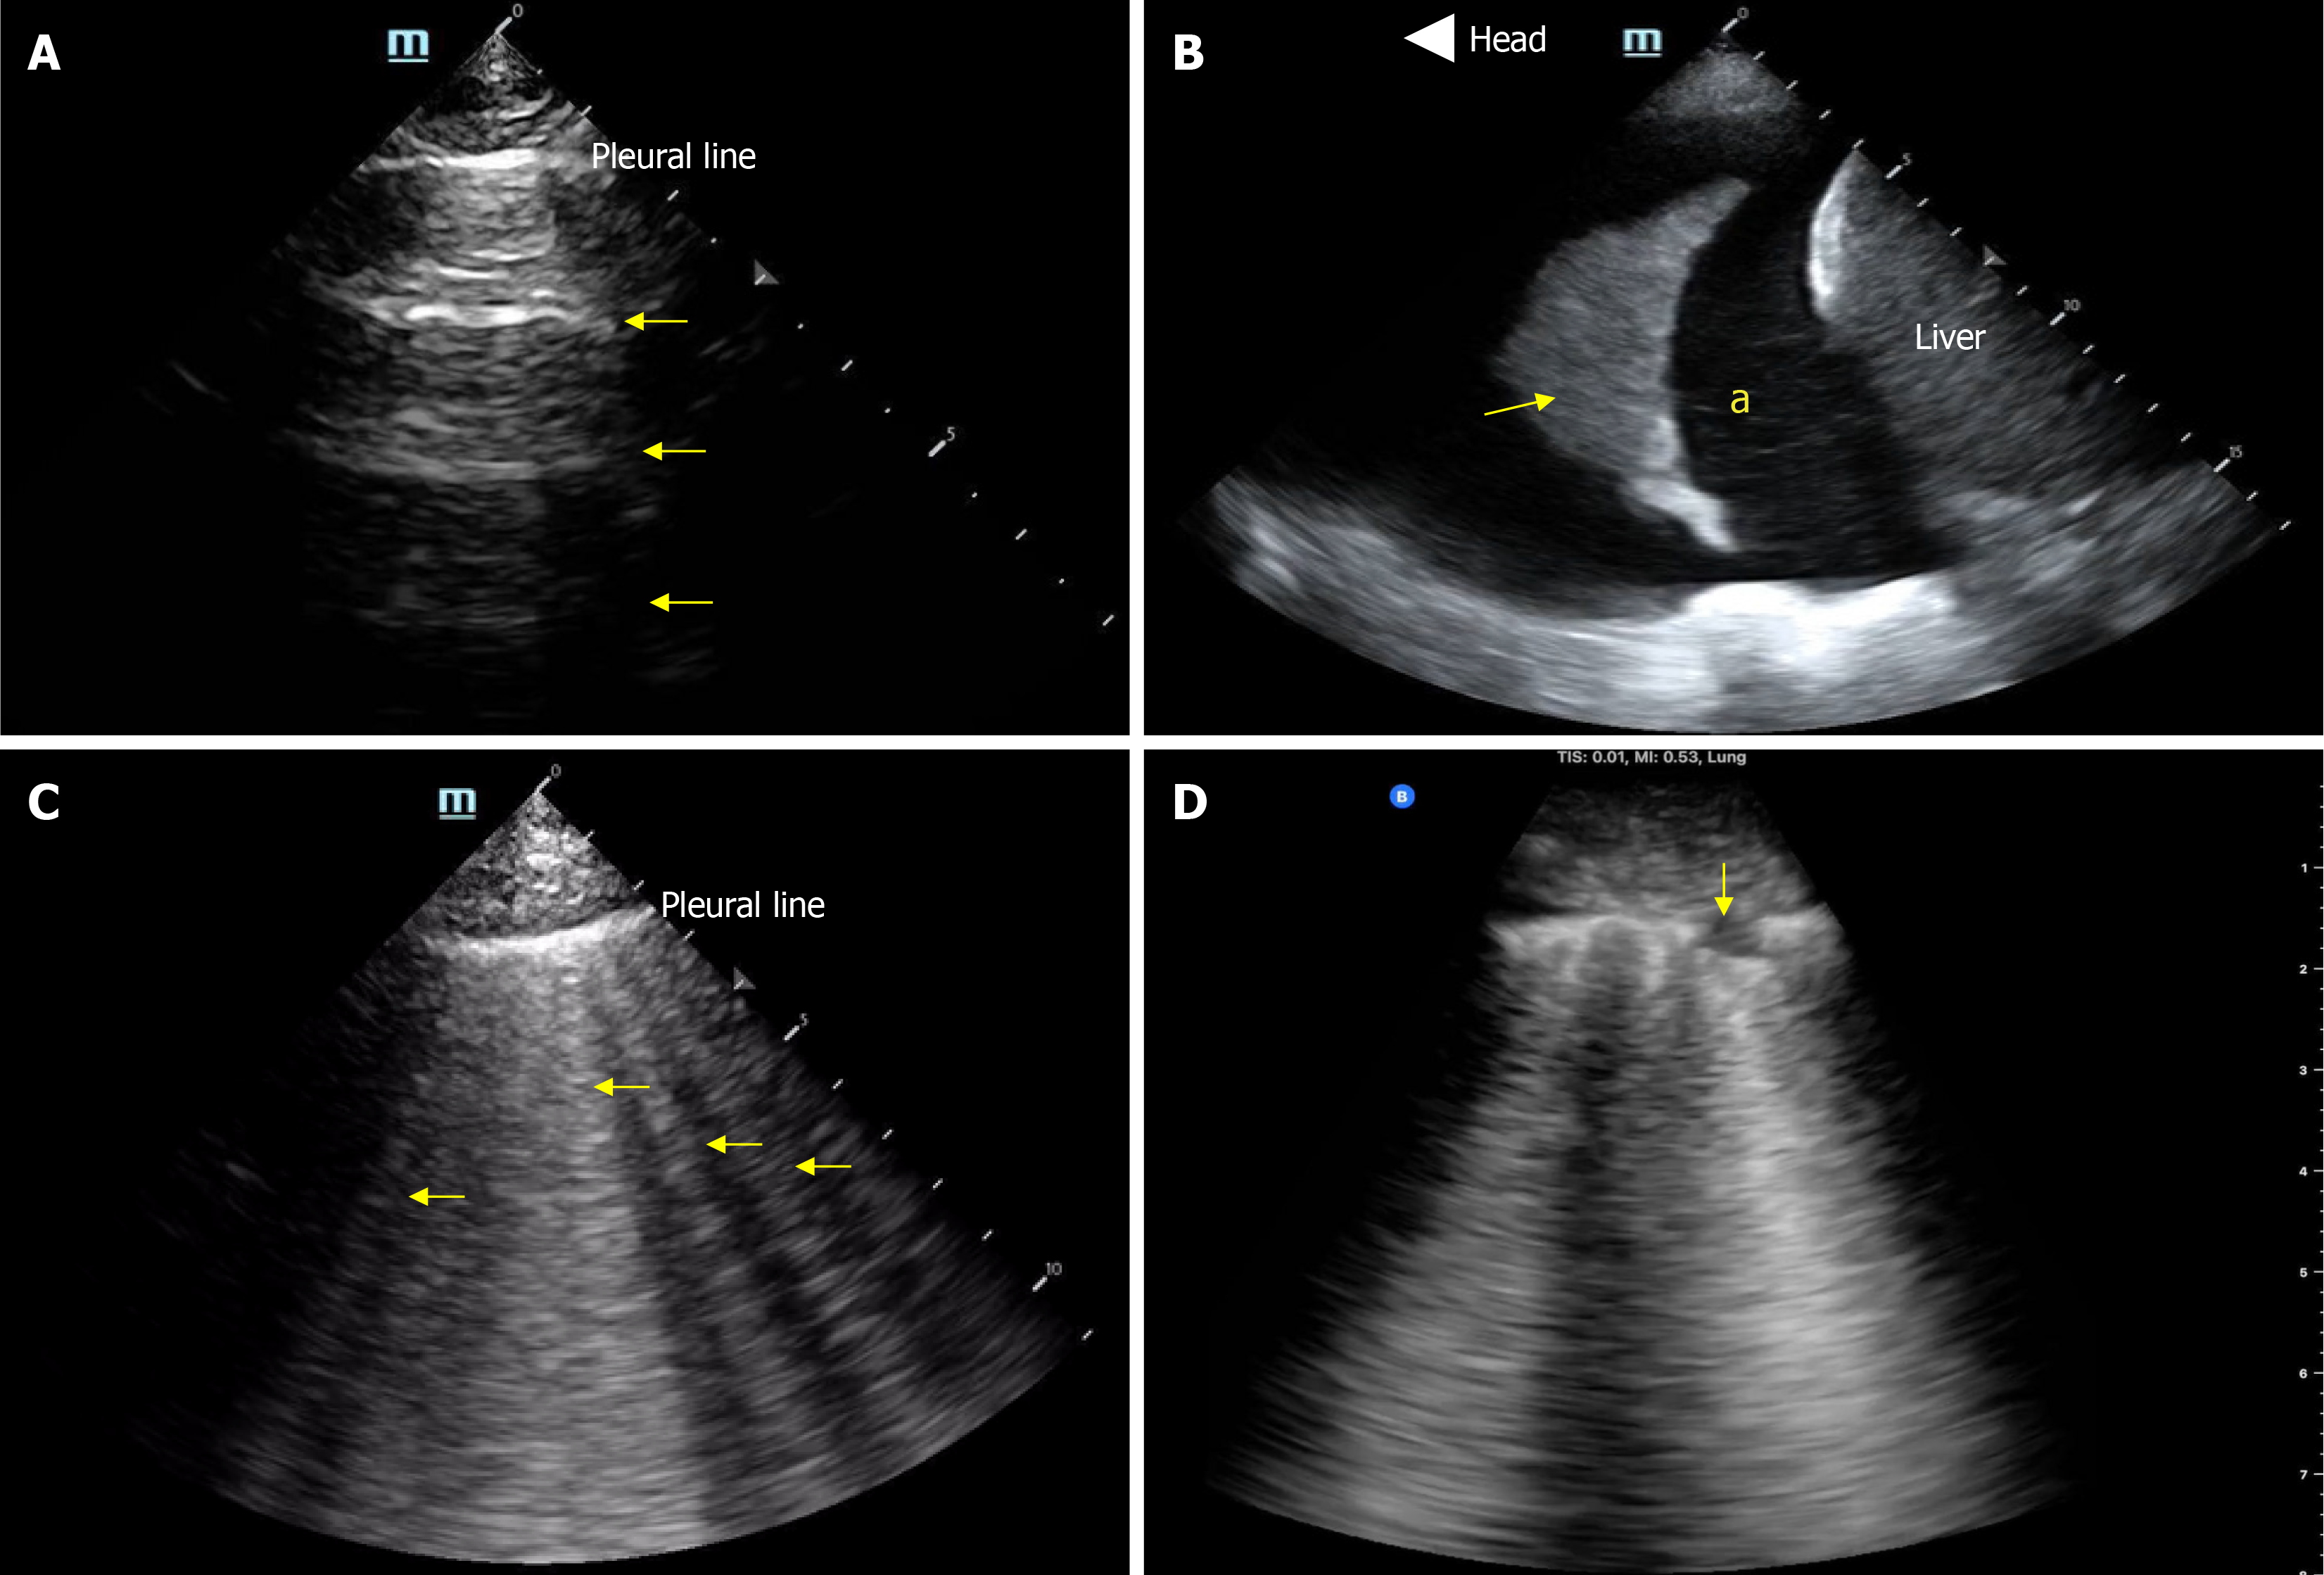

Lung ultrasound is another valuable tool for evaluating extravascular lung water. It has been shown to be more sensitive than chest radiography in detecting pulmonary congestion[36,37], and it holds prognostic value in heart failure, helping to monitor the effectiveness of decongestive therapy[38,39]. It is also technically simpler than cardiac ultrasound in terms of both image acquisition and interpretation. However, B lines, the vertical artifacts characteristic of pulmonary edema are non-specific and may also be seen in ARDS, pneumonia, pulmonary fibrosis, and alveolar hemorrhage[40]. In such cases, integration with Doppler-based assessment of left ventricular filling pressures is helpful as mentioned above. Figure 3 illustrates common pathologies identified by lung ultrasound.

Figure 3

Figure 3 Basic lung ultrasound findings. A: Normal lung with horizontal hyperechoic artifacts known as A-lines; B: Pleural effusion (asterisk) appearing as an anechoic area above the liver; the arrow points to atelectatic lung; C: Vertical hyperechoic artifacts called B-lines emerging from the pleural line, indicative of interstitial thickening typically due to fluid accumulation; D: Interstitial pneumonia, characterized by confluent B-lines and an irregular pleural line, with the arrow indicating a subpleural consolidation. Citation: Diniz H, Ferreira F, Koratala A. Point-of-care ultrasonography in nephrology: Growing applications, misconceptions and future outlook. World J Nephrol 2025; 25: 14: 105374. Copyright© The Author(s) 2025. Published by Baishideng Publishing Group Inc[29].